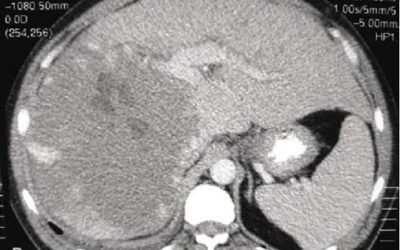

TOMOGRAFÍAS (TAC)

Cuando el diagnóstico es complejo o incierto, la Tomografía Axial Computarizada (TAC) se convierte en la clave.

Nuestro estudio de mayor tecnología y máxima precisión, capaz de revelar lo que otros métodos no logran detectar.

Realizamos:

- Abdomen

¿Por qué una Tomografía Computarizada (TAC) puede salvar tu vida?

La tomografía es una de las herramientas más precisas para detectar enfermedades en etapas tempranas. Permite evaluar el estado del cerebro, pulmones, abdomen, vasos sanguíneos y más con imágenes detalladas.En Ecodiagnóstica trabajamos con equipos modernos que reducen...